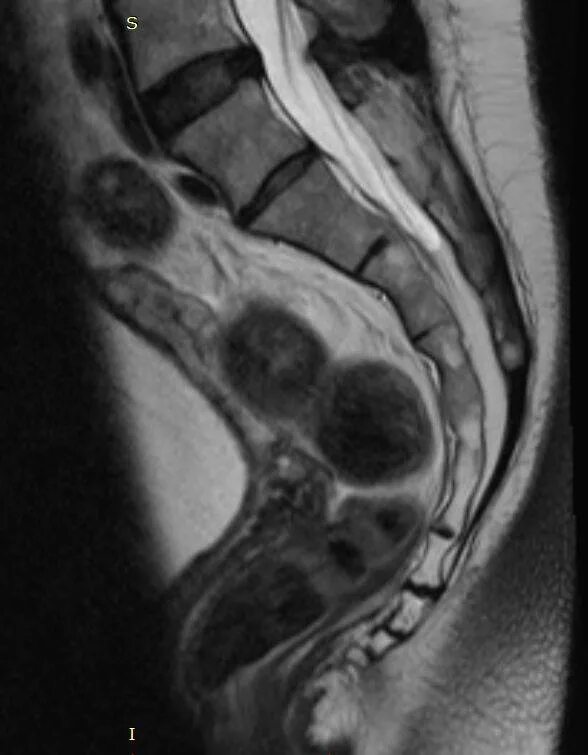

Снимок копчика